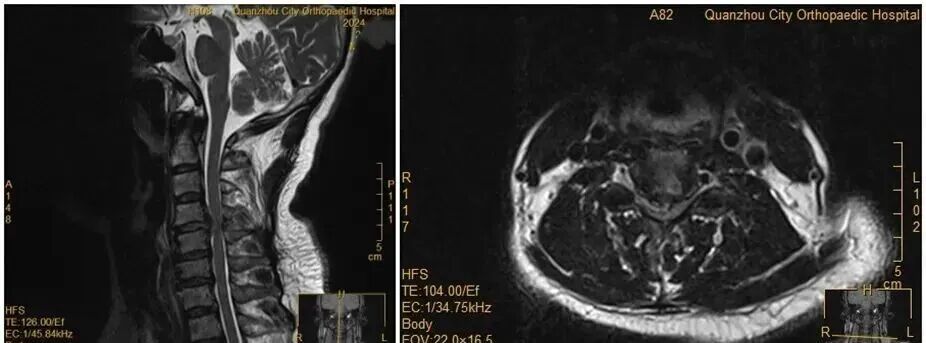

2025年12月,福建泉州50多岁的王女士因颈椎间盘巨大脱出引发急性脊髓压迫,在翻身拿手机的瞬间突发双上肢瘫痪,关键肌肌力骤降至0级。尽管紧急手术后恢复良好,但这场“意外”暴露了颈椎病的致命风险:看似普通的低头动作,可能成为压垮脊髓的最后一根稻草。

医生指出,王女士的颈椎MRI显示其椎间盘已严重脱出并压迫脊髓,保守治疗无法阻止病情恶化。若再拖延手术或颈部突受外力,可能造成永久性瘫痪。